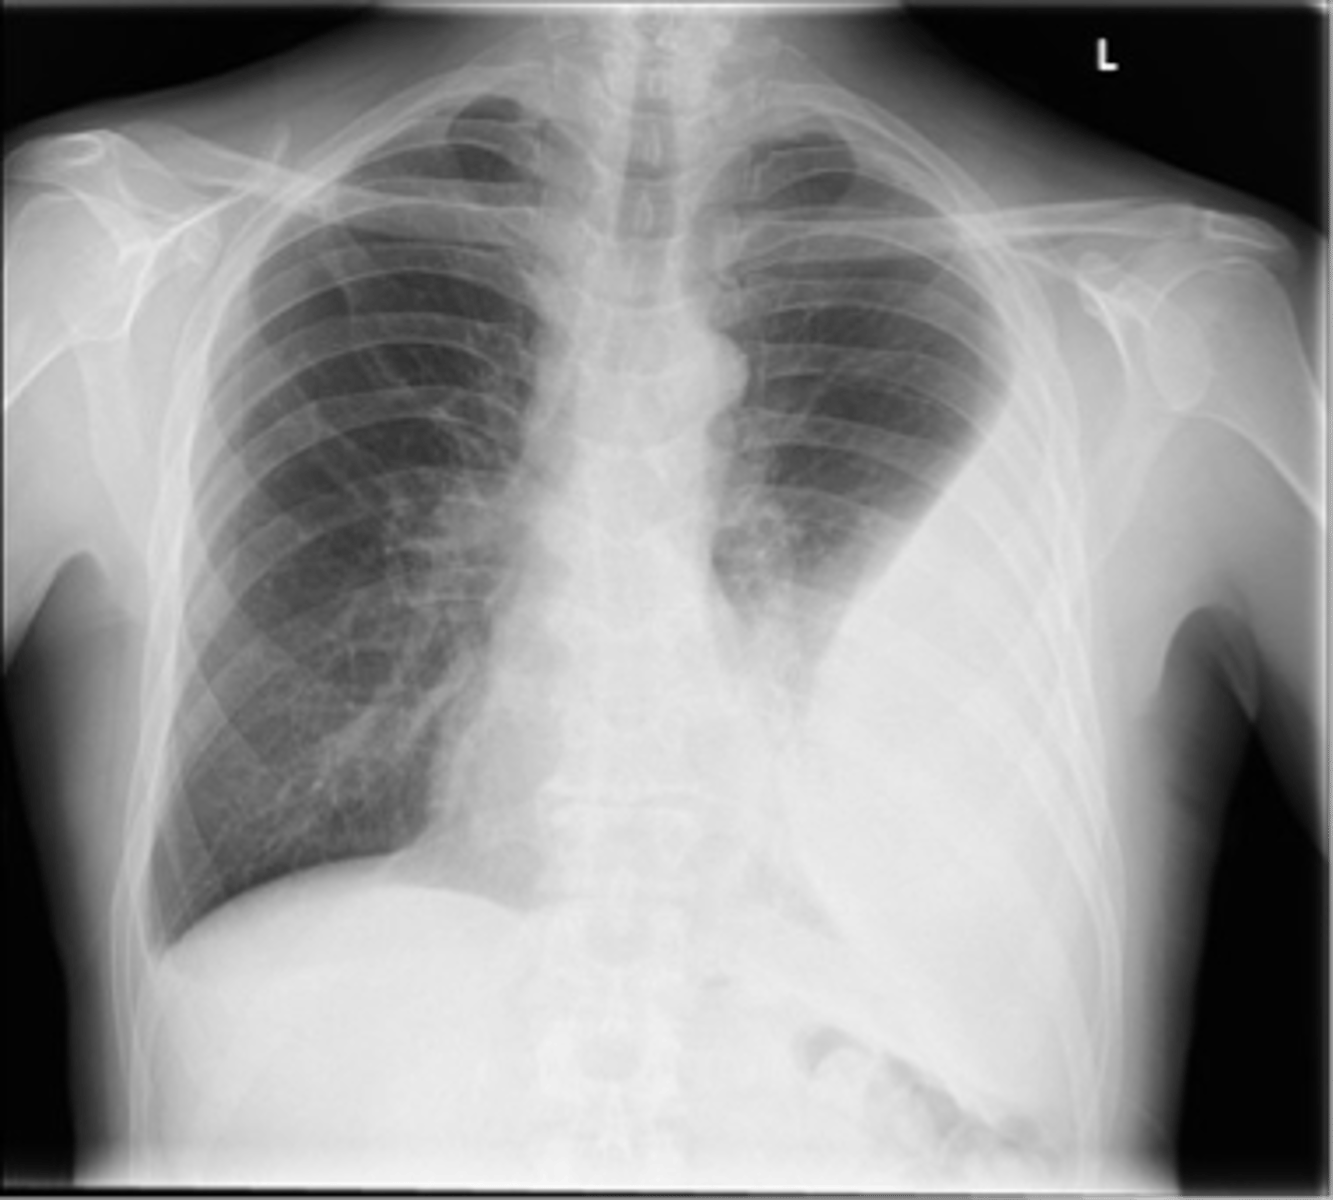

Flattening of hemidiaphragms

& blunting of costophrenic angles, Increased AP diameter (barrel chest), bullae or large air cavities indicates

hyperinflation

COPD/Emphysema

knowt flashcard image